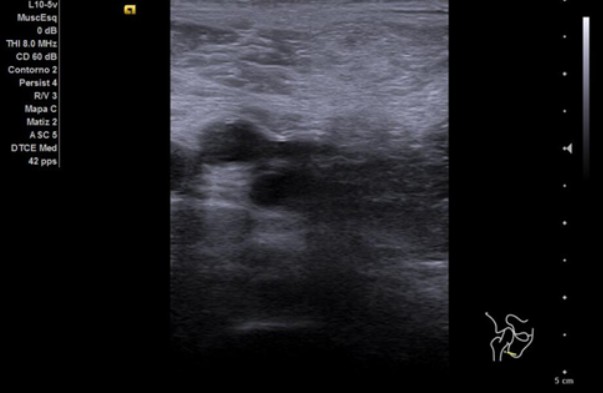

Se realiza ecografía clínica de rodilla derecha y se valora vena femoral derecha desde cayado hasta región poplítea.

A nivel vascular, se exploran ambas venas femorales desde cayado de vena safena hasta la región poplítea con maniobras de compresión mostrando un diámetro conservado, colapsabilidad completa y presencia de flujo a la activación del Doppler color. No se evidencian signos de trombosis venosa profunda.

A nivel articular, se observa líquido articular en zona subcuadricipital en cantidad leve moderada. Resto sin hallazgos relevantes.

La ecografía nos dio la posibilidad de descartar la sospecha de TVP en una paciente con edad avanzada y limitación de la movilidad tras ingreso prolongado. Además, se realizaron controles sucesivos de la artritis sin necesidad de desplazarse al Hospital, teniendo un seguimiento más estrecho, continúo y comparativo respecto a visitas previas. Así, aseguramos una mejor atención y un tratamiento más dirigido. Sin duda, la ecografía nos facilita el trabajo diario y ayuda a manejar la incertidumbre ante patologías potencialmente graves tiempos dependientes.